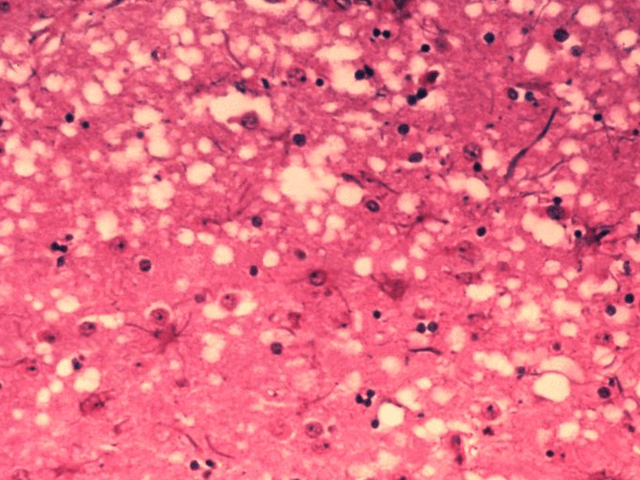

亲自领了一片长老的脑子,他发现这块脑片竟然如同一块布满空洞的海绵

克雅氏病(cjd)是一种罕见的致命脑部疾病,由让人闻风丧胆的朊病毒引起